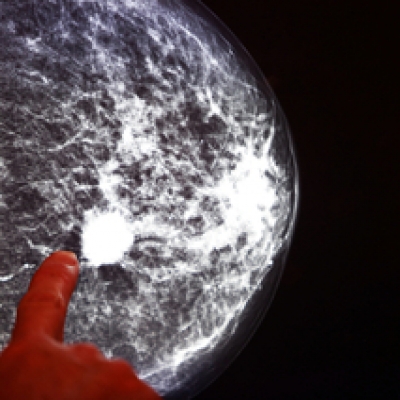

La diagnosi di fibroadenoma è però effettuata da esami specifici, tra cui i test di imaging a ultrasuoni al seno o la mammografia.